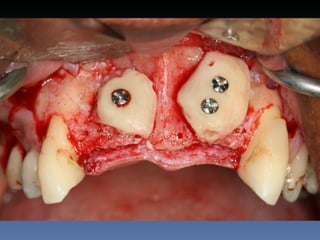

BOX 2

Silvia Maria Cardoso

Idade – 40 anos

Sexo – Feminino

Raça – Caucasiana

ASA – II

Data- 24-04-2012

Diagnóstico: Desdentada pré-maxila

Plano de tratamento:        Reabilitação com 2 blocos

“onlay” provenientes de Ilíaco fresco-congelado

(FFB); e posterior reabilitação protética fixa .